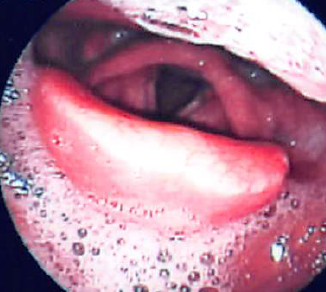

声帯ポリープとは

声帯炎の反復や声の酷使、喫煙などの慢性刺激により発症する病気でカラオケポリープとも呼ばれています。柔らかい腫瘤で多くは一側性です。保存的治療はあまり期待できません。

ポリープ様声帯

喫煙により声帯が浮腫状に腫大するブヨブヨな声帯で、低い粗造性嗄声です。まれに呼吸困難を生じます。また、喫煙者40歳以上の女性に多く認めます。

喫煙により声帯が浮腫状に腫大するブヨブヨな声帯で、低い粗造性嗄声です。まれに呼吸困難を生じます。また、喫煙者40歳以上の女性に多く認めます。